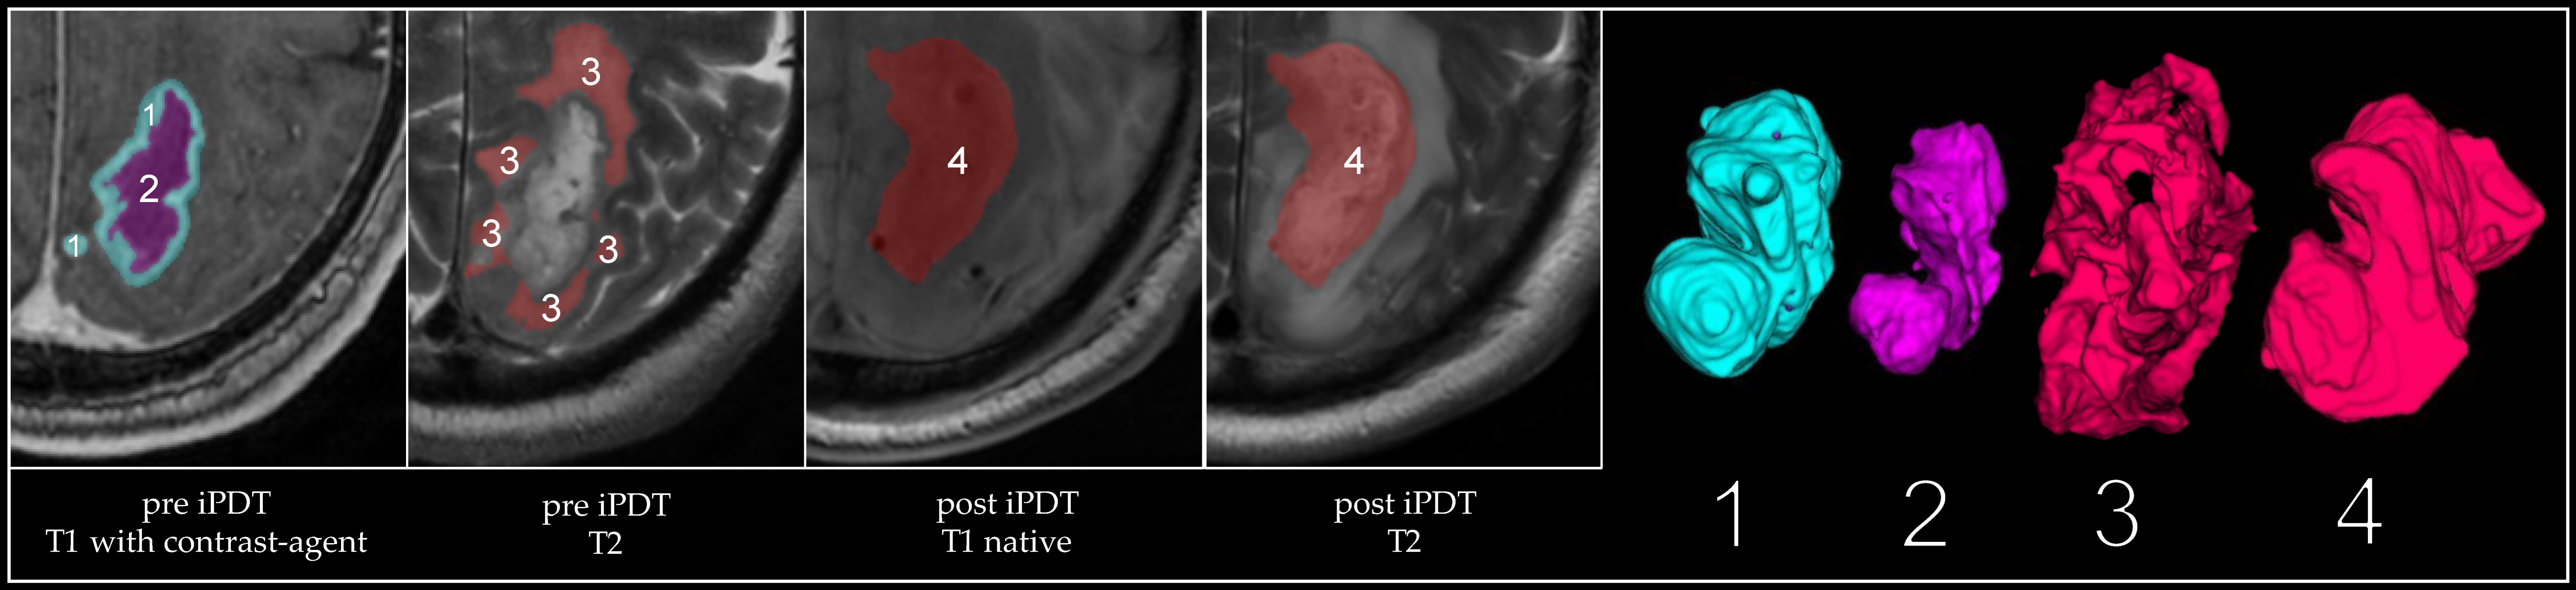

3.2. Volumetric Assessments

| Volume | Tumor Pre iPDT (mm³) | CE Pre iPDT (mm³) | Necrosis Pre iPDT (mm³) | CE 1 Day Post iPDT (mm³) | iPDT Remnant 1 Day Post iPDT (mm³) | iPDT Remnant 3 Months Post iPDT (mm³) | iPDT Remnant 3 Months Pre Recurrence (mm³) | iPDT Remnant at Recurrence (mm³) | Recurrent Tumor at Recurrence (mm³) |

|---|---|---|---|---|---|---|---|---|---|

| Median | 6063 | 3533 | 1350 | 535 | 12,426 | 5585 | 4036 | 3914 | 5893 |

| Average | 7622 | 5180 | 2442 | 1108 | 19,166 | 7151 | 4474 | 4556 | 6645 |

| Max | 21,825 | 12,362 | 9463 | 4720 | 66,857 | 20,027 | 12,254 | 9607 | 17,177 |

| Min | 1362 | 878 | 118 | 0 | 2062 | 370 | 305 | 157 | 6 |

| SD | 5849 | 3761 | 2579 | 1463 | 16,571 | 5395 | 3188 | 2917 | 6115 |